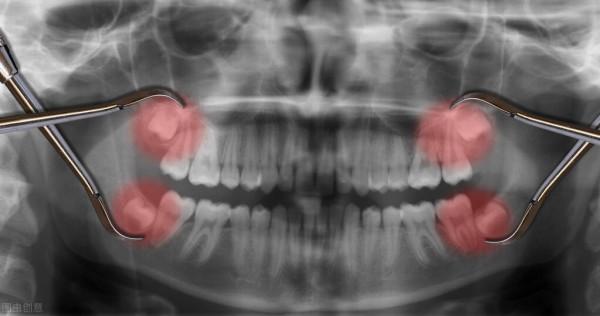

正因為是這樣,所以猿類最終進化為人類,不過在進化的過程中,既然出現了5處不完美的地方,第一個不完美的地方就是智齒,可能很多朋友有智齒,一般智齒出現的年齡是在16到30歲之間,智齒不僅沒有給人類帶來智慧,反而給人類帶來了很多麻煩,智齒非常容易蛀牙,一旦蛀牙之後就會很疼,一般醫生都建議拔掉智齒,所以智齒對於人類來說沒有好處竟是壞處,第二個不完美的地方是氣管,氣管和食道是人體最重要的兩個器官,我們在呼吸的時候和吃飯的時候都要用到它們。